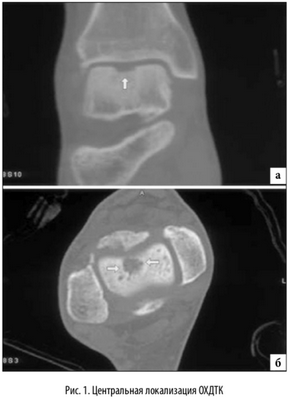

Наиболее распространенной локализацией остеохондральных повреждений таранной кости является переднелатеральной и заднемедиальной край суставной поверхности таранной кости. Исследование, основанное на изучении МРТ данных, проведенное Hembree с соавт. [14], определило, что большинство выявляемых локализаций остеохондральных повреждений таранной кости располагались медиально и центрально [15]. Независимо от этого, латеральная локализация данных повреждений связана с травмой от 93% до 98% случаев. Однако, было отмечено, что повреждения латеральной локализации в основном имеют меньшую и правильную овальную форму и возникают при эверсионных движениях в максимальном подошвенном сгибании стопы [16]. Медиальные повреждения связаны с острой травмой реже, от 61% до 70% [5]. Считается, что медиальные поврежде ния, вызваны повторяющейся микротравмой, вызванной соударением медиального края суставной поверхности таранной кости о суставную поверхность большеберцовой кости в момент максимальной супинации стопы. Медиально локализующиеся повреждения глубже, кратерообразной формы, и образуются при максимальном подошвенном сгибании стопы [16]. Остеохондральные повреждения с центральной локализацией имеют мультифакторный механизм образования и наиболее сложны в плане хирургического лечения (рис. 1).

На КТ определяется остеохондральное повреждение таранной кости.